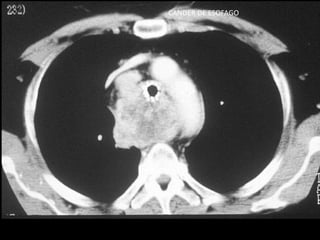

CANDER DE ESOFAGO

MTS GANGLIONARES

• Ubicación: mas frecuente en mediastino medio

• Edad: 60 – 70 años

• Clínica: efecto de masa

• Orígen:

– 80% de CA de pulmón

– 18% de otros CA intratorácicos

– 2% de CA extratorácicos

• Diagnóstico: mediastinostoía, mediastinoscopía, VATS

• Tratamiento: QTX

MTS GANGLIONARES • Ubicación:mas frecuente en mediastino medio • Edad: 60 – 70 años • Clínica: efecto de masa • Orígen: – 80% de CA de pulmón – 18% de otros CA intratorácicos – 2% de CA extratorácicos • Diagnóstico: mediastinostoía, mediastinoscopía, VATS • Tratamiento: QTX